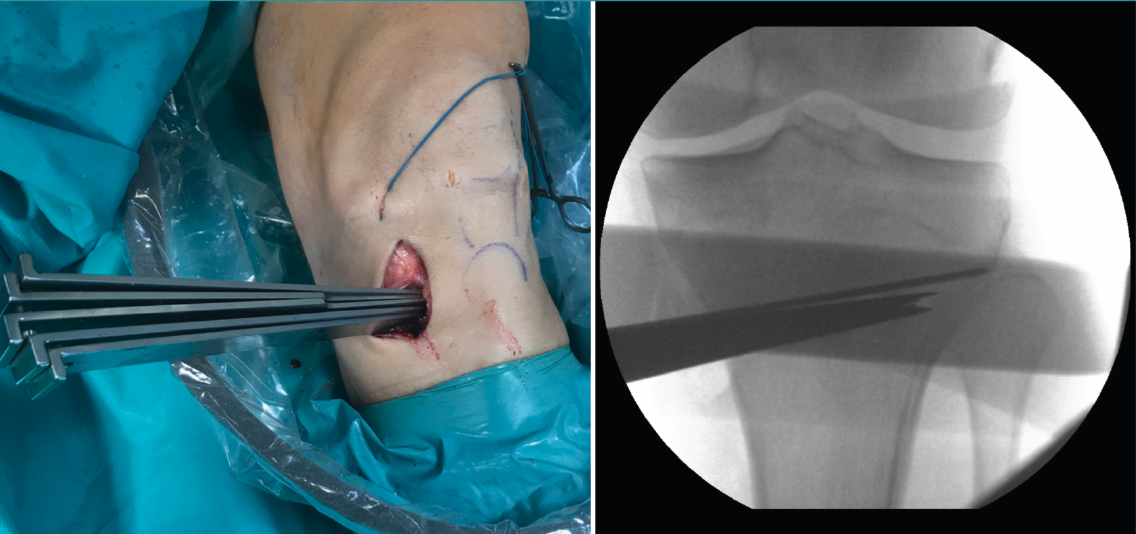

Posteriormente, bajo control radioscópico, se realiza la osteotomía apoyando la sierra por debajo de la aguja guía, llegando hasta 1 cm de la cortical lateral. Se introducen los escoplos para abrir la osteotomía (Figura 4). El primer escoplo, el más ancho, se introduce primero para comprobar el corte completo de la cortical posterior. Seguidamente, se coloca el medidor del ángulo de apertura (Figura 5A) y, a continuación, se introduce el distractor en la parte posterior de la osteotomía, evitando así un aumento de la PTP (Figura 5B). En este momento, se puede introducir en la apertura de la osteotomía el aloinjerto o sustituto óseo. Los autores utilizan aloinjerto óseo cuando la apertura es mayor de 10°. Antes de colocar y fijar la placa de osteotomía, se realiza el túnel tibial utilizando las herramientas artroscópicas clásicas (Figuras 6A y 6B). Al realizar una osteotomía biplanar, el corte es suficientemente distal como para permitir brocar el túnel tibial de la RLCA sin dificultades.

Figura 4. Colocación de escoplos de forma progresiva para realizar la apertura (una vez realizados los cortes con la sierra).